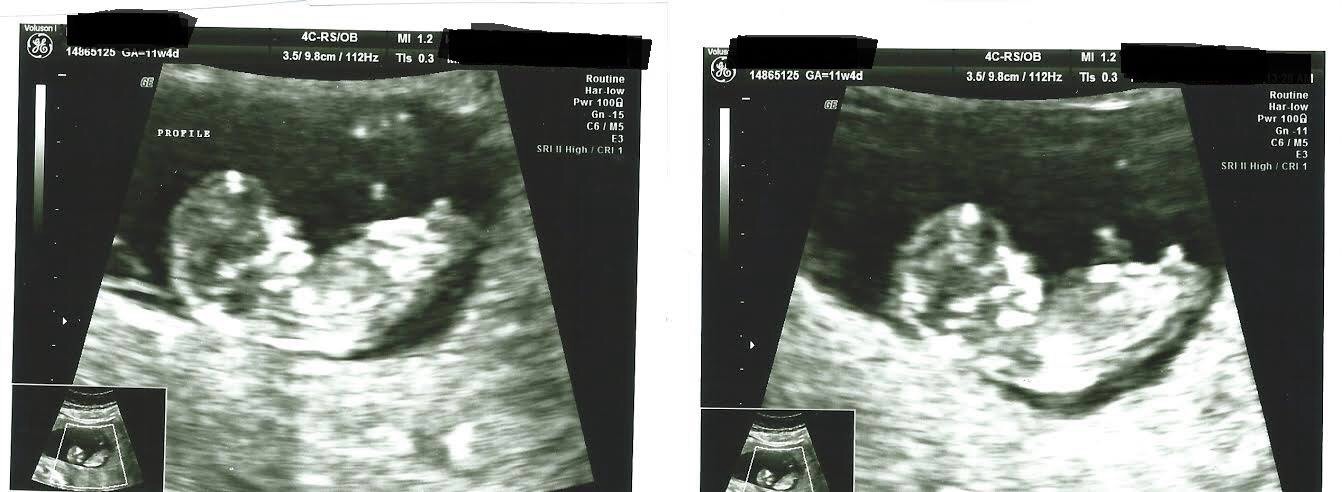

Please guess gender.. 11 weeks 4 days

I know it was early and Baby had legs and butt in the air but im hoping there is at least a lean even though its early.. When we were watching the ultrasound screen the nub was chunky and short and i want to say angled but the babys spine makes me doubt myself.

Is it even likely that a boy nub would already be shorter and thicker this early? Does this look boyish even as early as it is or girly or 50/50 :/. Im 13 weeks tomorrow but my nt scan "had" to be done at 11 weeks 4days..i have 3 weeks until i know and im going nuts.